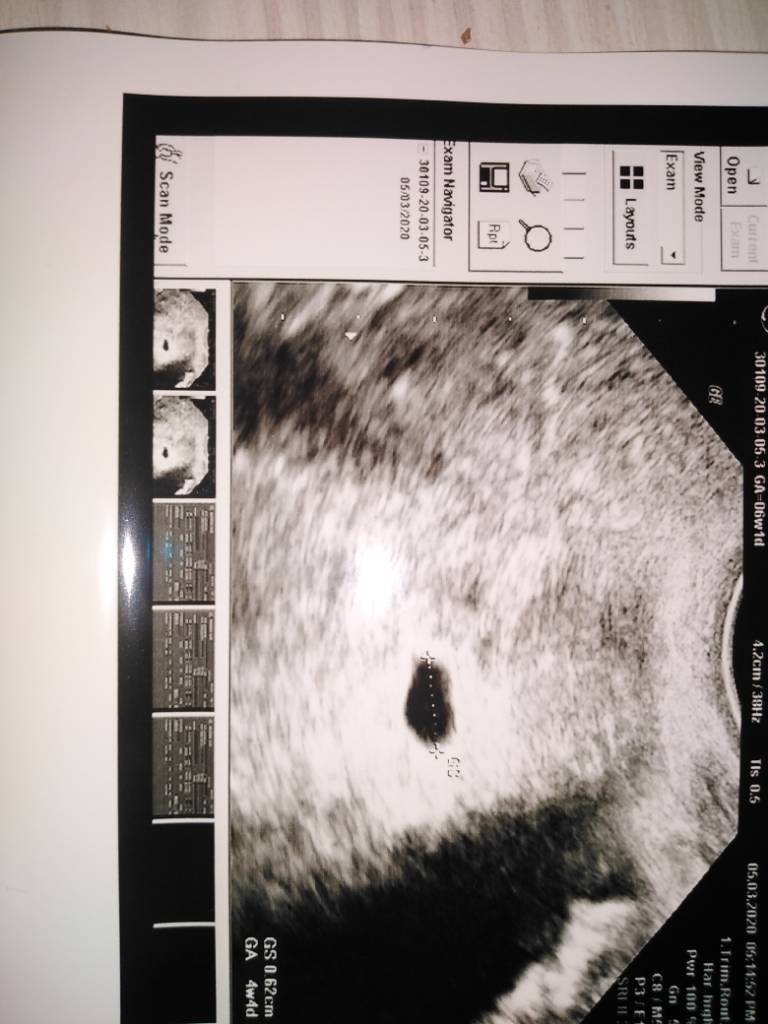

Jest tylko pecherzyk ciazowyA jest ciało żółte?

Nie nie ma zarodkaCzyli nie ma jeszcze zarodka ? Tak? Na to wychodzi.Ale ja bym na Twoim miejscu poszła do innego gina.Po moim ostatniej wizycie na izbie przyjęć byłabym ostrożna co do kierowania się opinią jednego lekarza.

Idź dla pewności gdzie indziej.Ja wiem sama po sobie ,że już bym nie zaufała jednemu lekarzowi...Nie nie ma zarodka